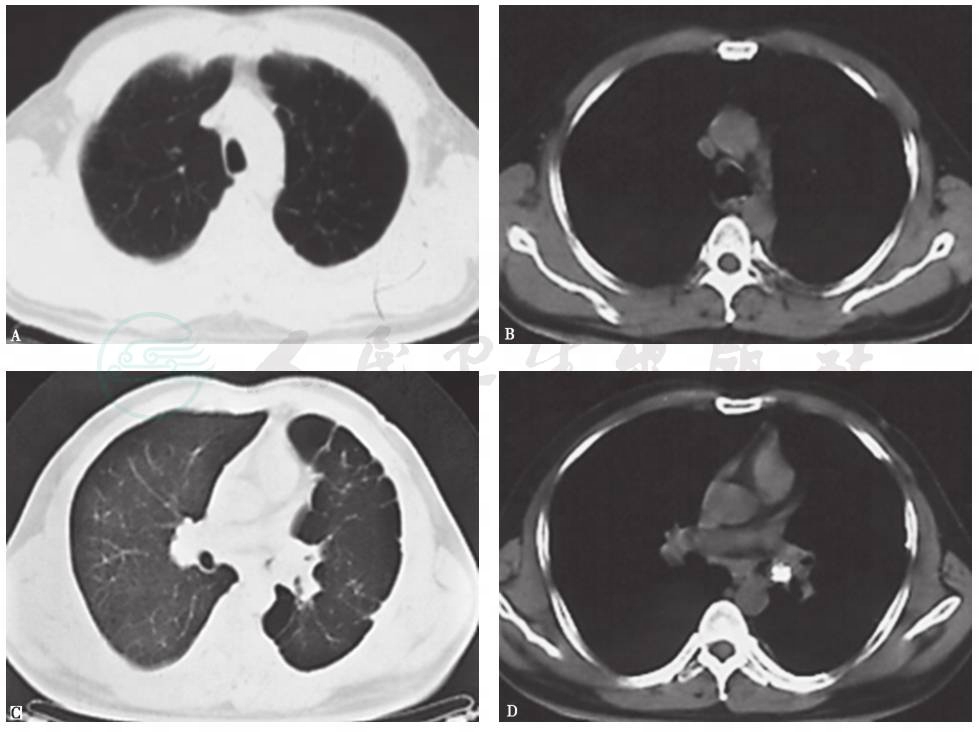

入院1个月前,胸部CT见左侧多发肺大疱,左下肺脓肿,其内见液平,左主支气管腔内高密度影,左侧少量胸腔积液(图1),抗感染治疗后未见好转(图2)。

图2 抗感染治疗后复查胸部CT表现

5.先后经多种抗感染治疗,患者症状及胸部影像学表现均无好转。